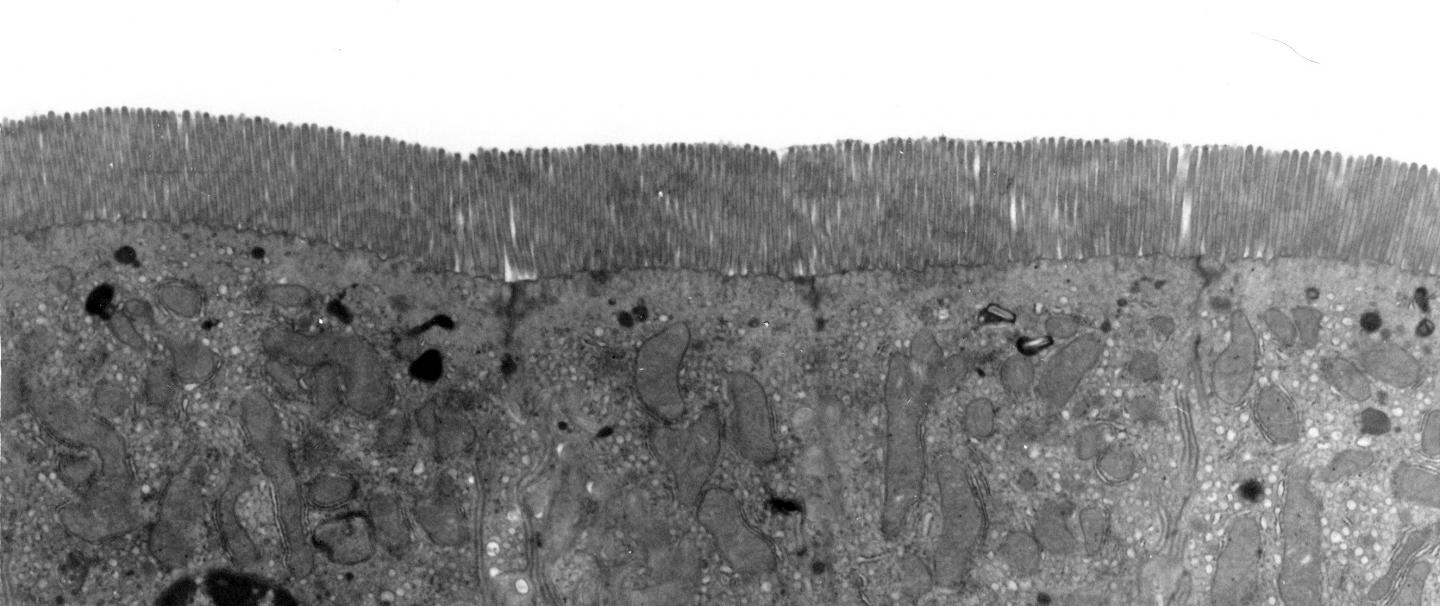

As well as digesting food, the gut plays a central role in programming our immune system, and provides an effective barrier to bacteria that could make us ill. In particular, immune cells that line the gut work to maintain the integrity of the barrier, as well as maintaining a balance that provides a healthy environment for beneficial bacteria, but reacts to combat invasion by pathogenic microbes.

Further experiments showed that the increased levels of IL-6 directly lead to making the gut barrier 'leaky' to small, soluble molecules, although no physical differences in its structure were seen. And the scientists also showed that aging is associated with a reduced immune response to microbes, which might contribute to our increased susceptibility to infection as we age.